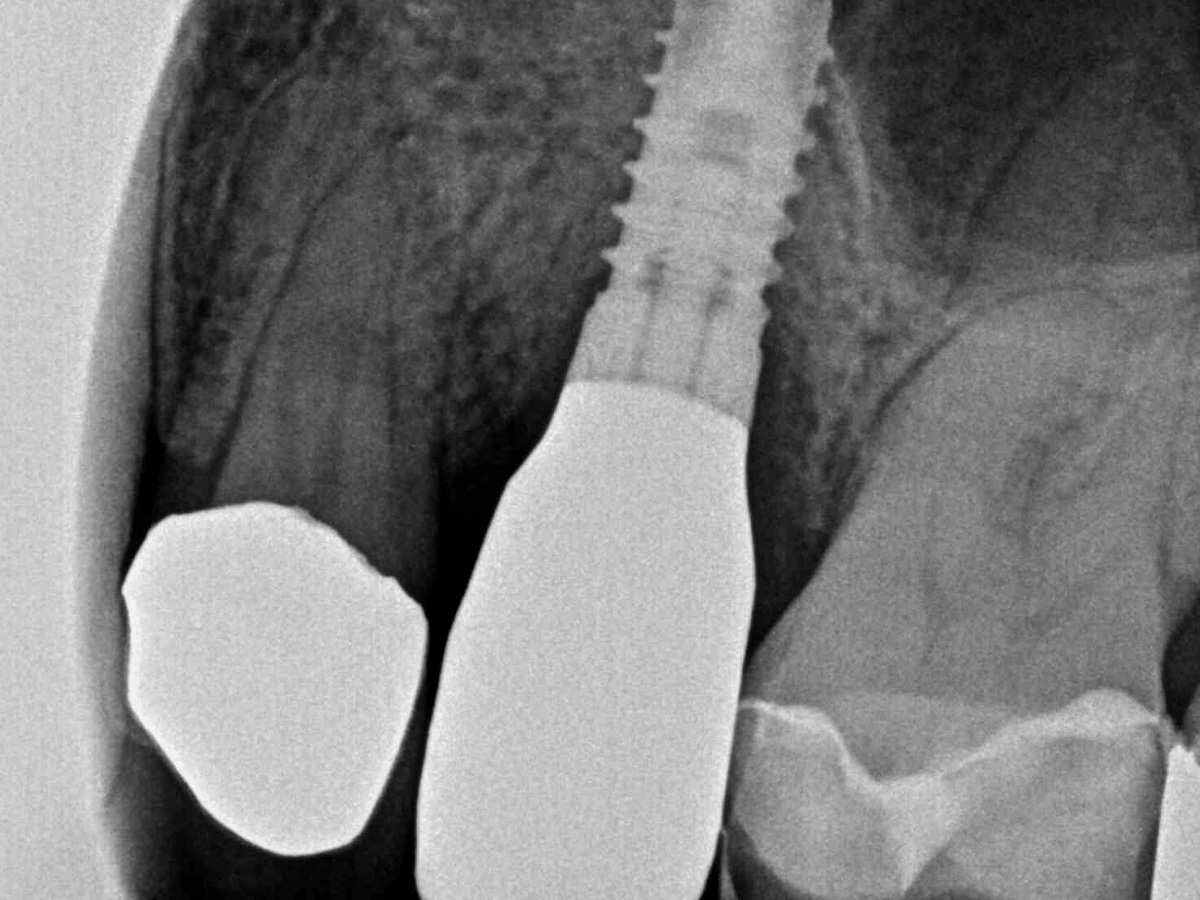

Abbildung 17

Abschlussröntgenbild